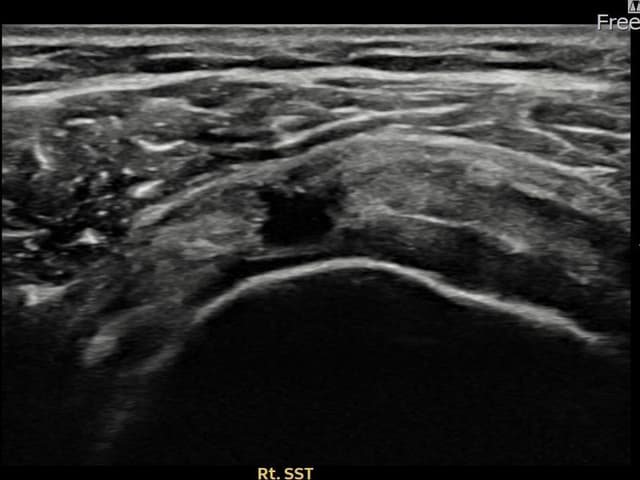

右侧 冈上肌腱 石灰化肌腱炎

10mm × 7mm